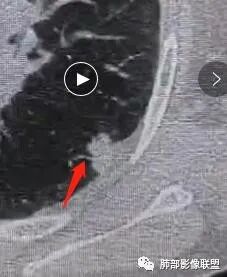

这条血管让我不踏实,像脐凹征吗?

就是这个脐凹征有恶性的特点,所以恶性肯定不能排除

一、本例恶性征象较有特征的是脐凹征。

1.脐凹征:分叶状结节局部凹陷的部位受到血管阻力而形成,表现为血管进入分叶之间,脐凹相对比较对称光滑,近肺门侧多见,与血管走行方向一致。

2.95%见于恶性肿瘤,5%为炎性病变。